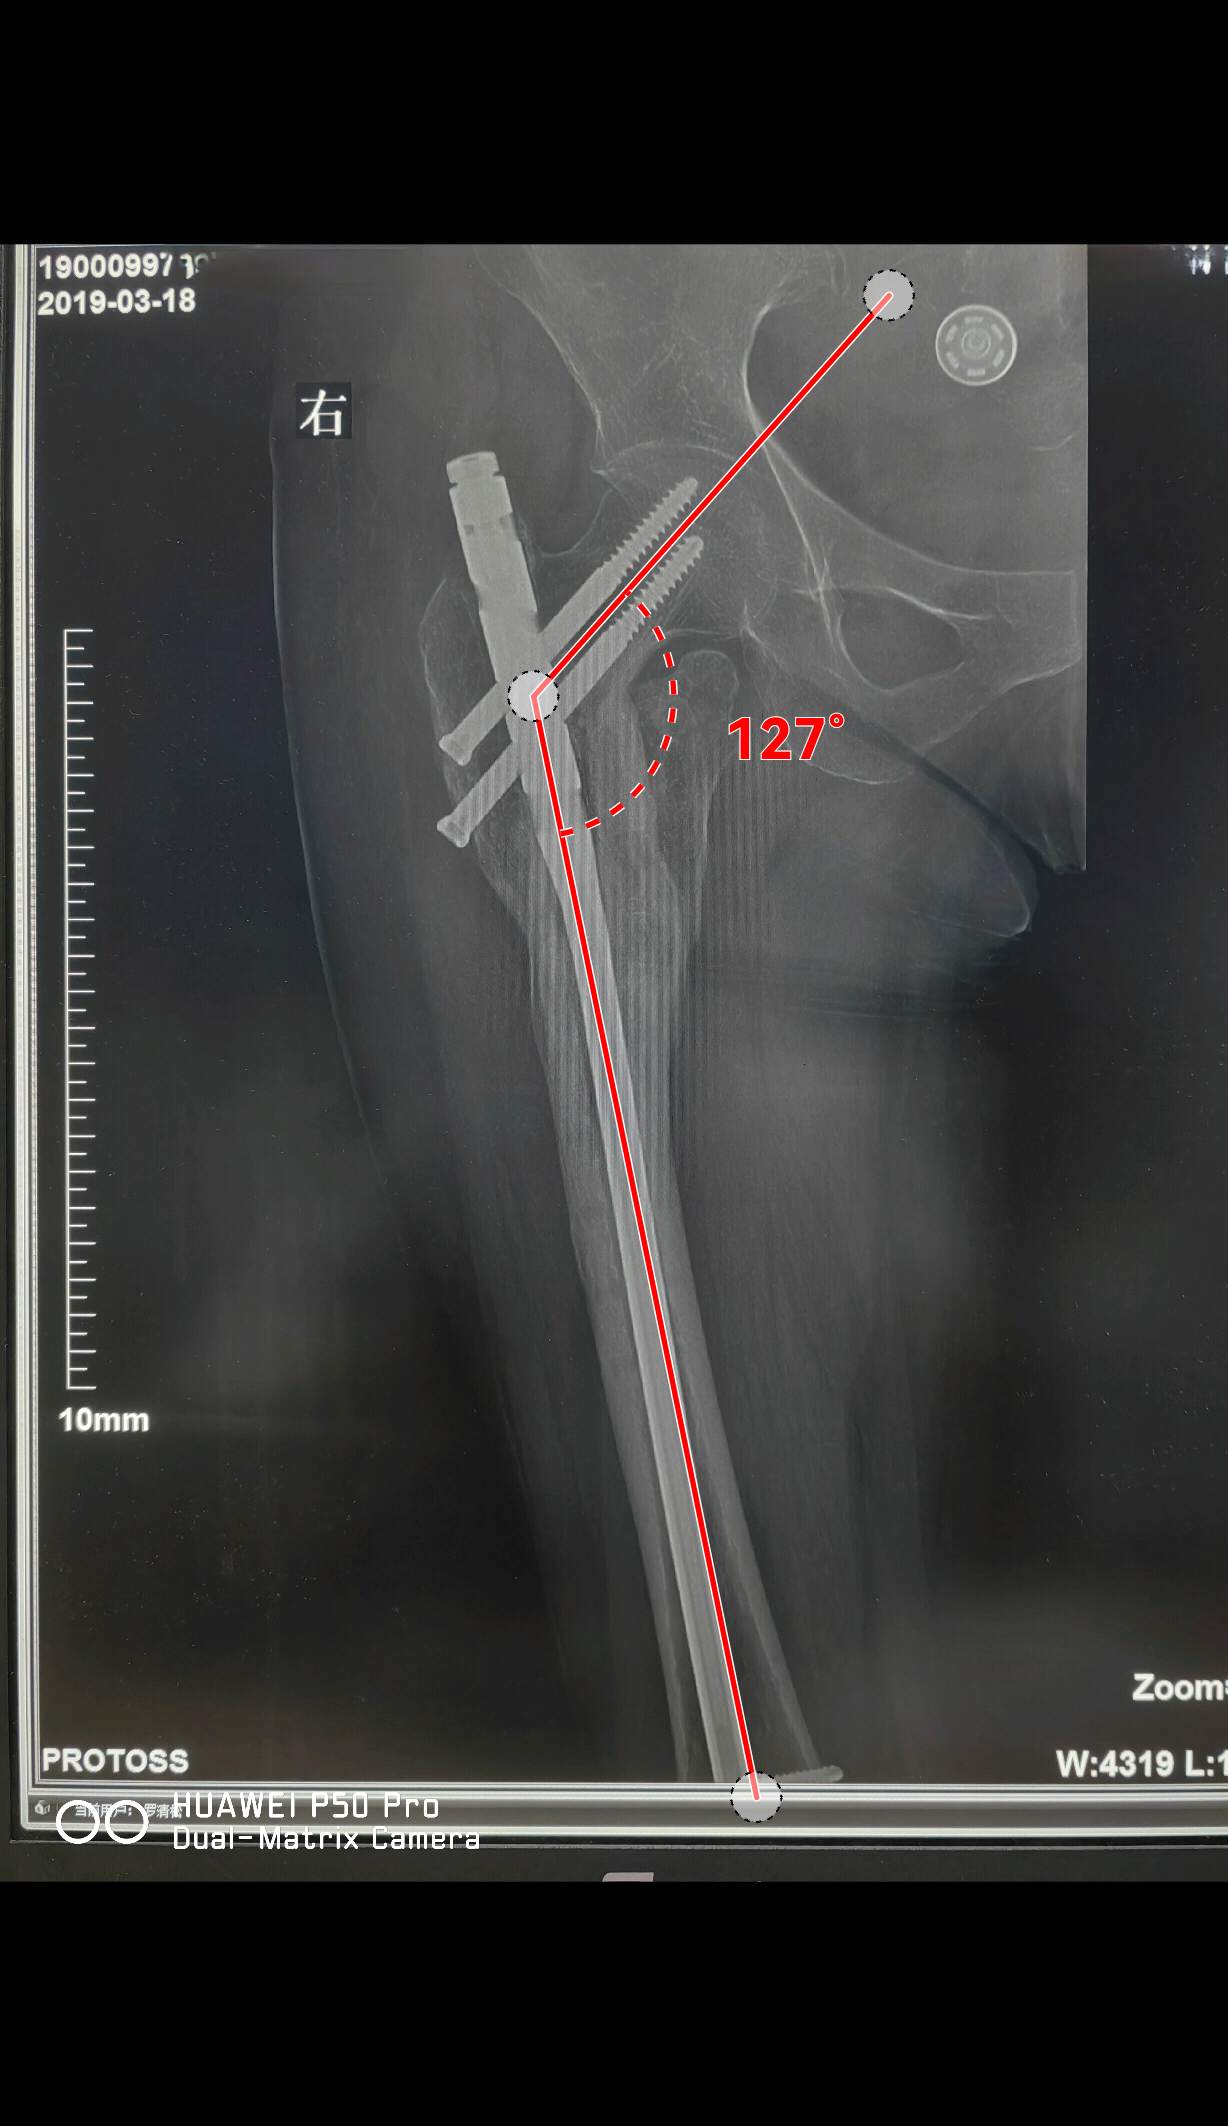

四个月后

骨折愈合良好

术后一年

骨折完全愈合